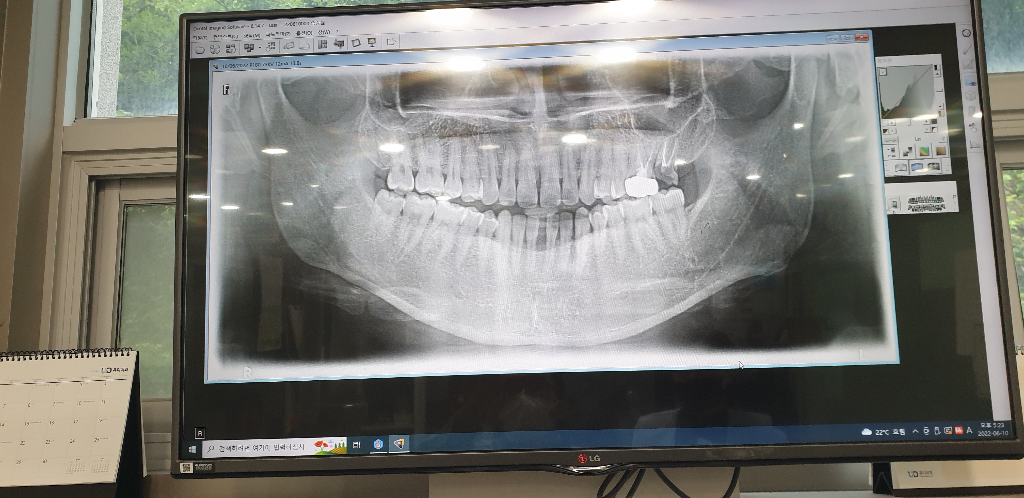

저의 치아상태입니다 .....

현재 지금은 이런모습을 띄고 있습니다

제 개인적으론 인플란트를 1개 박고 싶은데 치과 의사마다 소견이 달라서요

왼쪽 위 제일 마지막 어금니는 치아가 파절된 상태로 뽑고 임플란트 해야 할 것으로 보입니다.

현재 사진으로는 특별히 다른 부위에 문제는 없어 보이며 왼쪽 위 맨 마지막 어금니만 발치를 하시고 임플란트를 진행하시면 될 것으로 보입니다. 사진상으로 다른 부위에 특별한 문제가 보이지 않고 맨 왼쪽 위 2번째 치아 상태 역시 판단하기 어렵습니다. 따라서 지금 사진만으로는 해당 부위만 발치하고 임플란트가 가능할 것으로 보입니다.

파노라마 사진상으로 보면 왼쪽위 젤뒤 어금니는 신경치료후 치아가 깨지신거 같습니다. 이같은 경우에는 발치하시고 임플란트 하시는게 좋을것같습니다.

현재상태를 봐서는 발치후 임플란트를 해야할것으로보입니다.

발치후 3개월정도 기다린뒤에 할수도 있고,발치와 동시에 식립할수도 있습니다. 다만 동시식립시 골이식이 필요할 수 있습니다.